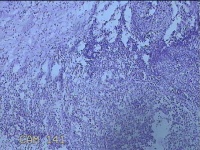

右侧会阴部结节

性别

女

年龄

31岁

临床诊断

皮脂腺囊肿

一般病史

发现右侧会阴部结节2个月。

标本名称

大体所见

灰白暗红色结节1.7x1.3x0.3cm一个,表面糜烂,切开结节呈实性,切面灰白暗红色,质软。

图4

炎症性病变。